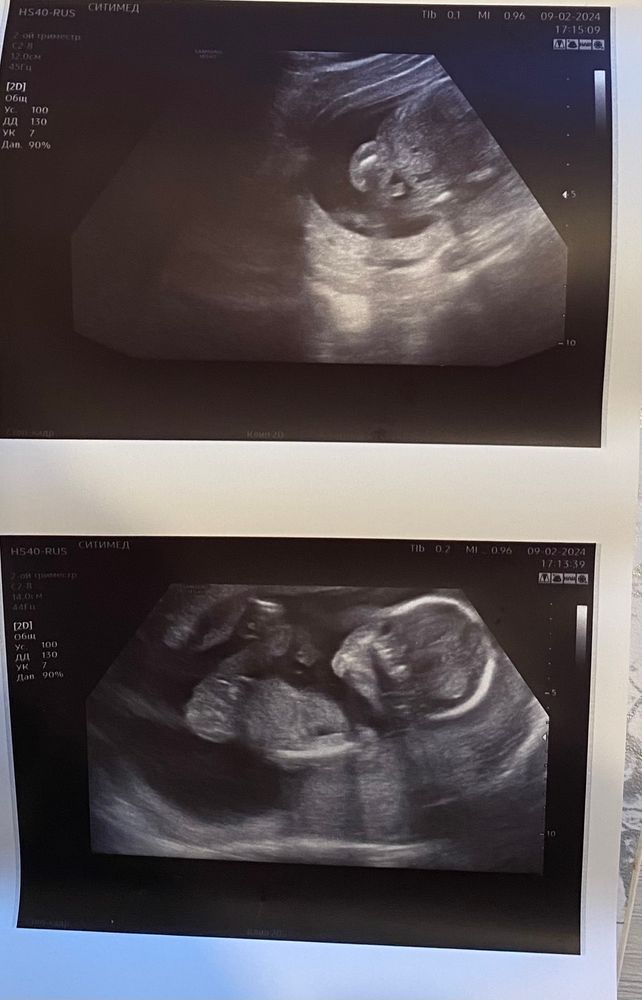

Всем привет!Вчера были на узи, срок 16.3 дня, врач говорила не пойму , и не девочку и на мальчика, все держит между ног и пуповину и руки.Но мне кажется по фото там явно мальчик.